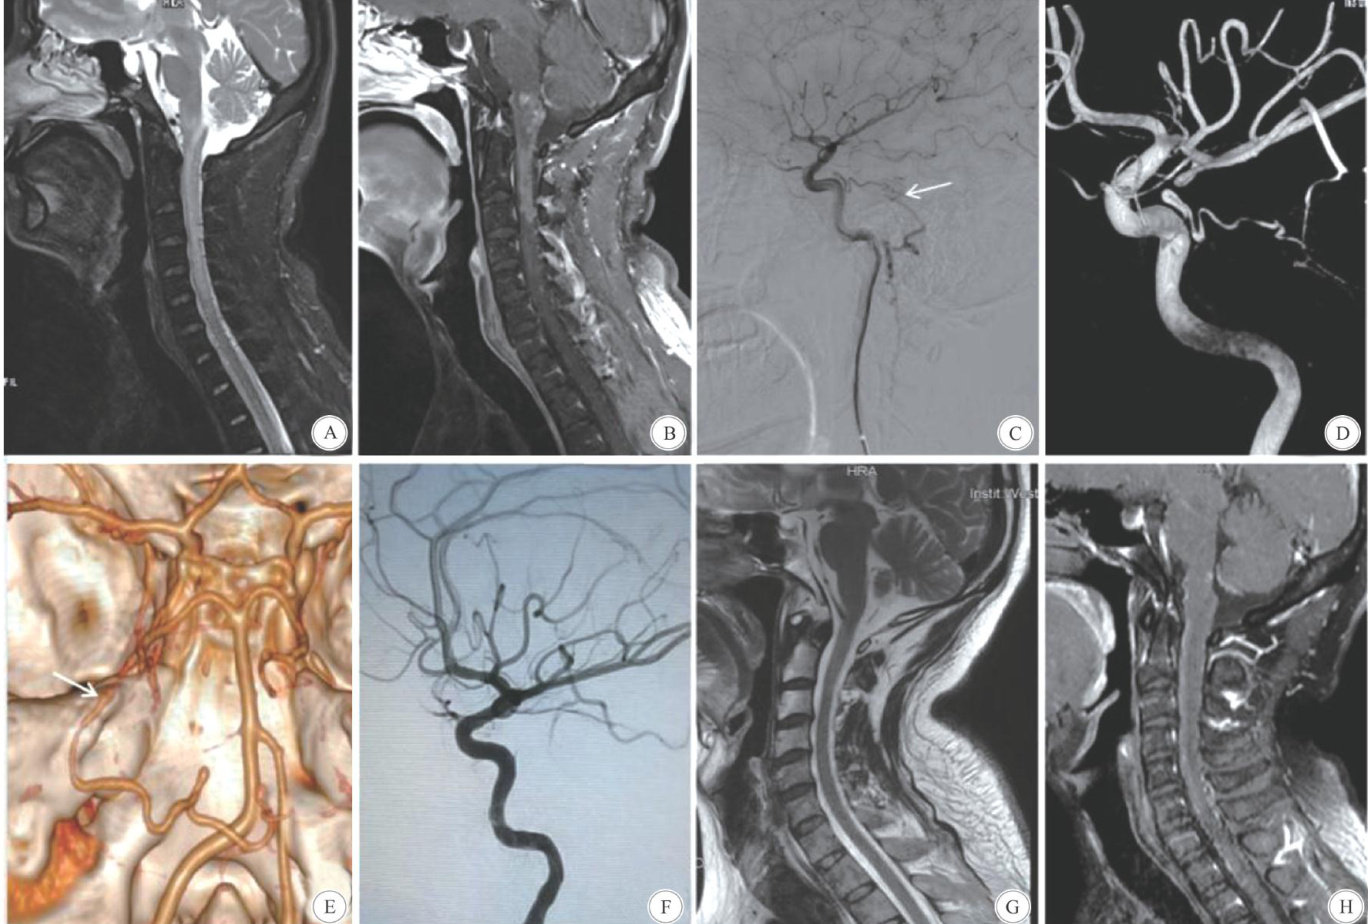

Abstract: ObjectiveTo investigate the clinical features,imaging features and diagnosis and treatment Cognard Type V inracranial dural arteriovenous fistula(DAVF). MethodsThe clinical and imaging data 12 patients with Cognard Type V DAVF admitted to Hospital,Sichuan University,from January 2O17 to January 2O25 were retrospectively analyzed. Brain MRI and digital subtraction angiography(DSA) were performed in all patients before operation,and the final diagnosiswas confirmed.The treatment methods were surgical ligation the fistula and interventional embolization. ResultsThe main symptoms were diferent extents paralysis the lower limbs,limb paresthesia and bladder and bowel dysfunction. The main findings MRI were brain stem and cervical spinal cord edema and vascular flow voids on the surface spinal cord. The fistula was located in superior petrosal sinus in 5 cases, the foramen magnum area 7 cases. Blood supply arteries mainly came from the meningohypophysial stem the internal carotid artery,the middle meningeal artery,the ascending pharyngeal artery,and the meningeal branch the vertebral artery. The drainage vein mainly drained through the veins on the surface the brain stem to the anterior and posterior veins the spinal cord.The treatment included surgical resection in 8 cases and interventional embolization in 4 cases. There were no complications. Postoperative follow-up showed symptoms improved in 1O cases ( 83% ),stabilized in 2 cases (17% ),and no aggravation. Postoperative MRI showed that spinal edema subsided to different degrees and vascular empty flow disappeared. ConclusionsCognard Type V DAVF is clinically rare,and is easy to be missed and misdiagnosed because its nonspecific clinical manifestations. Spinal cord edema and vascular flow voids showed on MRI images are important clues for the diagnosis.DSA is stillthe golden standard diagnosis.Early diagnosis and aggressive treatment can prevent irreversible neurological damage.